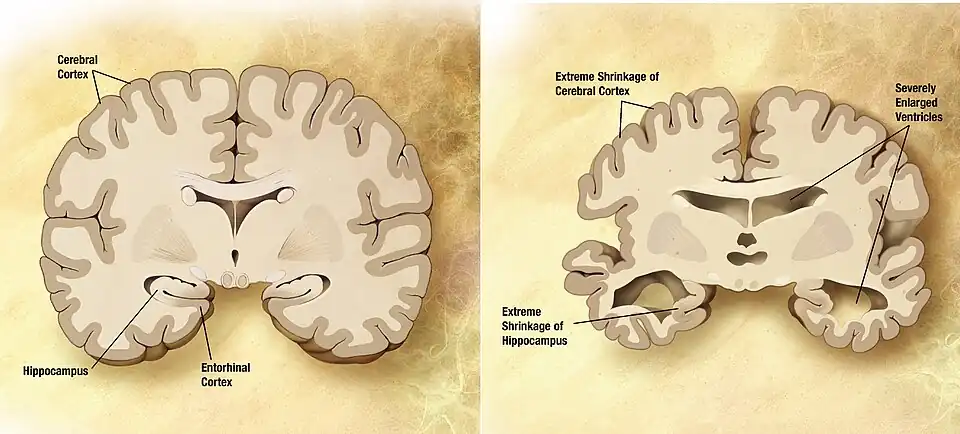

Alzheimer's is the most common form of dementia, especially for the elderly, with 70% of dementia sufferers having Alzheimer's. Others include Lewy Body and Vascular dementia, which differ from Alzheimer's in how they affect the brain and a person's functioning (Petersen, 2009). The changes that occur in Alzheimer's affect the brain and are irreversible. Treatments may slow damage and early intervention may prevent symptoms but once there it cannot be cured. The damage has multiple causes. Naturally occurring chemicals and proteins within the brain build up over decades. These proteins, most importantly amyloid, slowly build up in the brain. The resulting tangles then causes various dysfunctions, such as memory problems, through the disruption of nerve cell connections (Wolfe, 2007). First affected is hippocampal formation, which is intimately involved with memory. Fluid also accumulates in spaces where neurons have died causing brain shrinkage(Hoffman, Froemke & Golant, 2010), which can be seen in Figure 1. Also important is oxidative damage, which is a byproduct of oxygen being used by the cells. This is highly influenced by diet and will be explained in more detail later (Cotman, 2009). The changes in functioning can be viewed on a PET scan such as that in Figure 2.